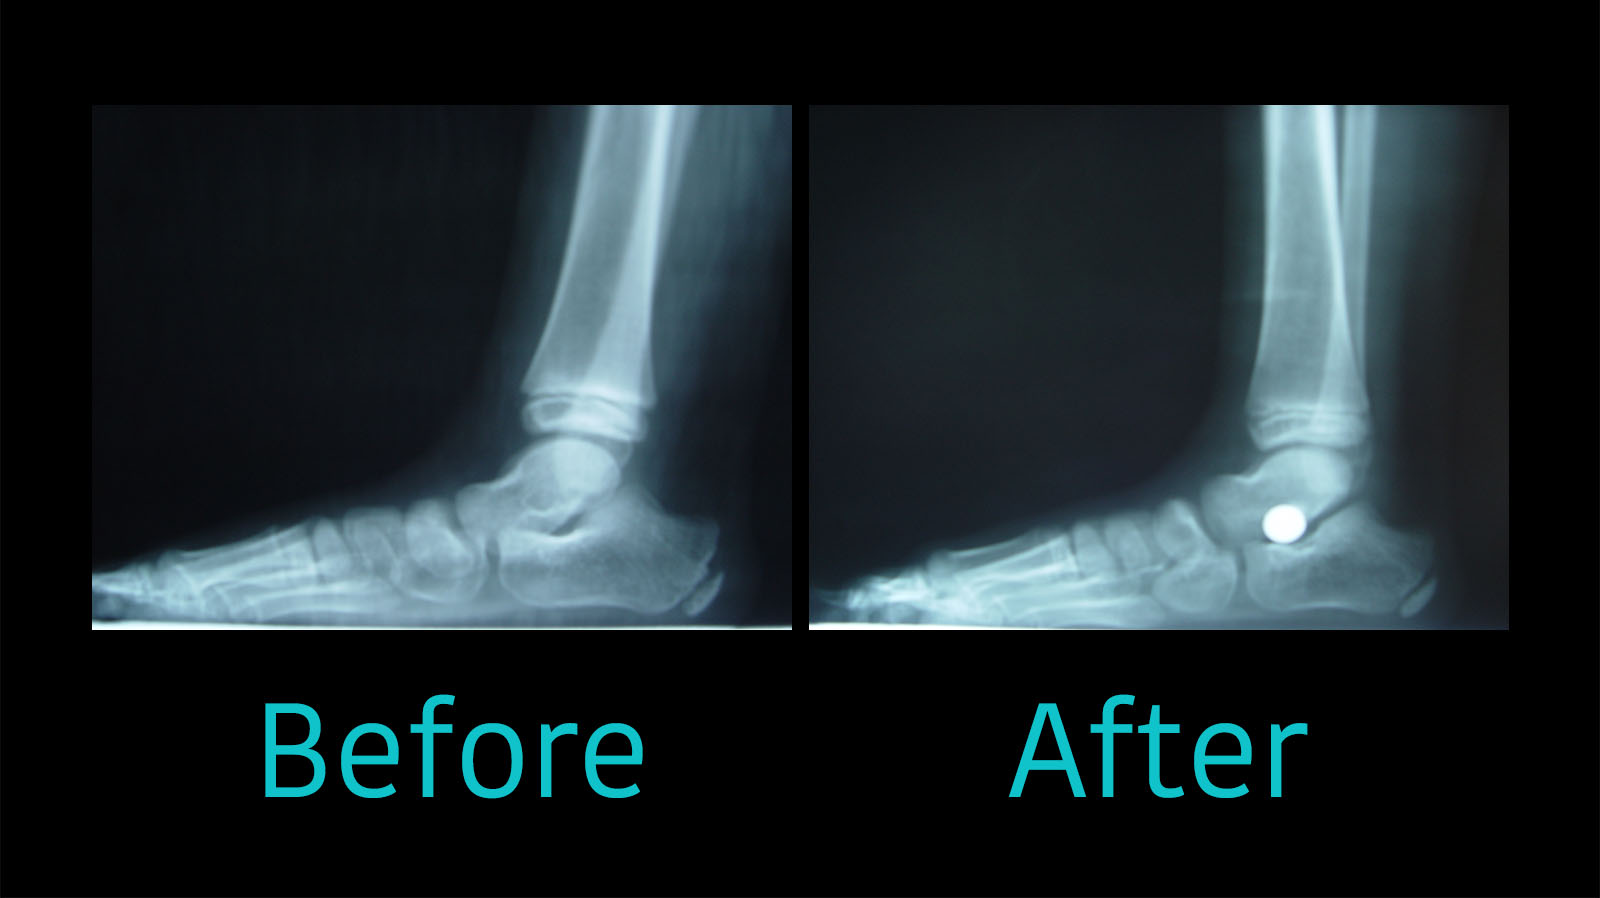

Flat Feet Reconstructive Surgery + Before and After YouTube What Is Flat Feet Surgery What is flat foot surgery? The condition may be inherited (runs in the family) or acquired (developing over time, most often as a result of age or injury). Flat foot surgery aims to restore the arch at the base of the foot. Surgery may involve cutting bones, replacing tendons, or strengthening ligaments. Usually, one foot is operated on at a.. What Is Flat Feet Surgery.

Flatfoot Surgery and HyProCure The Foot and Ankle Clinic What Is Flat Feet Surgery Flatfoot surgery addresses the bones, ligaments, and tendons that support the arch, often through a combination of procedures. Surgery isn't done solely to correct flatfeet. Surgery may involve cutting bones, replacing tendons, or strengthening ligaments. Surgery may be an option when patients have pain that still limits their activities after. Usually, one foot is operated on at a. Flat foot. What Is Flat Feet Surgery.